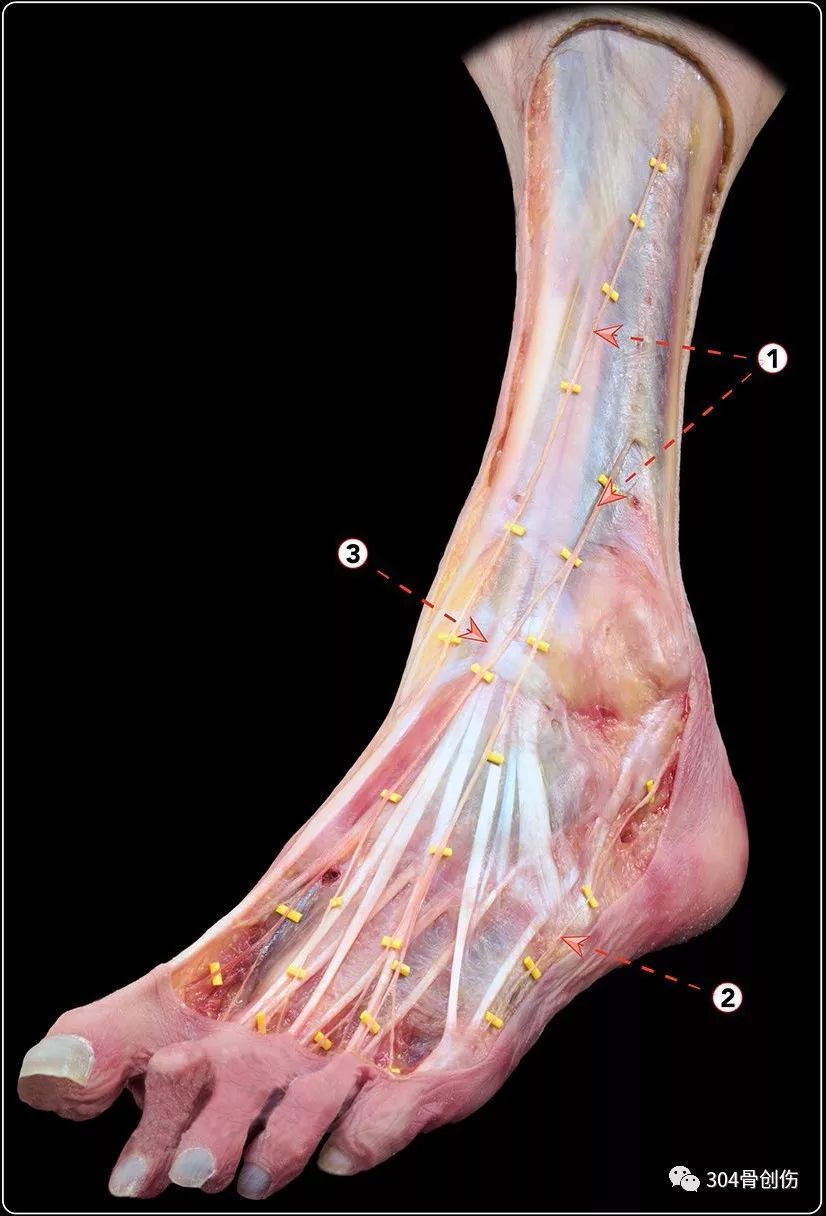

踝关节不稳定4踝伸肌下支持带解剖

图片尺寸826x1216